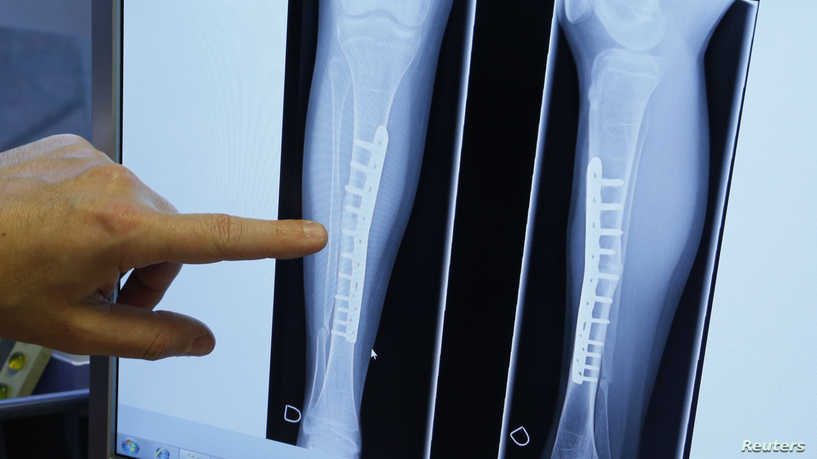

وفقا للدراسة التي أجراها علماء في جامعة أكسفورد البريطانية ونشرتها صحيفة “ديلي ميل”، فإن الأشخاص الذين يعتمدون على النبات في نظامهم الغذائي أكثر عرضة للكسور على مستوى العظام بنسبة تصل لـ 43% من الأشخاص الذين لديهم نمط غذائي اعتيادي، وترتفع هذه النسبة على مستوى العظام الرئيسية لتصل إلى 59%.

وجدت الدراسة التي أجريت على ما يقرب من 55 ألف شخص من الرجال والنساء، أن النباتيين أيضا معرضون لكسور على مستوى عظمة الفخذ بشكل أكبر من آكلي اللحوم بنسبة 25%.

يفسر العلماء هذه الظاهرة إلى أن عظام النباتيين أضعف؛ لأنهم لا يتناولون منتجات الألبان كالحليب والجبن والتي تعطي جسم الإنسان الكالسيوم، حيث تؤثر هذه المادة على كثافة العظام، تحديدا في سن البلوغ.